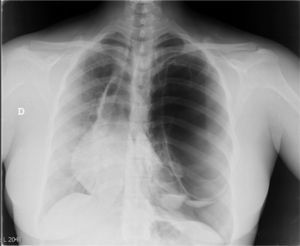

A 31-year-old woman from Pakistan with no significant clinical history consulted due to pleuritic pain of two days duration in the left hemithorax, radiating to the ipsilateral flank with mild hemoptysis. On arrival in the emergency room, she had 38° fever and chills. On auscultation, reduced breath sounds were found on the left side, and accordingly a chest X-ray was performed (Fig. 1, see figure legend).

In view of the radiological image, the chest surgery unit of the reference center was contacted and an angio-CT was performed. This showed voluminous bullae and cystic lesions in the left hemithorax of up to 20cm in diameter, with atelectasis of the pulmonary parenchyma, patent bronchi and air-fluid level in the left pleural space, and left anterior and basal pneumothorax; the right lung showed small subpleural nodules measuring less than 1cm in upper and lower lobes and normal pleural cavity.